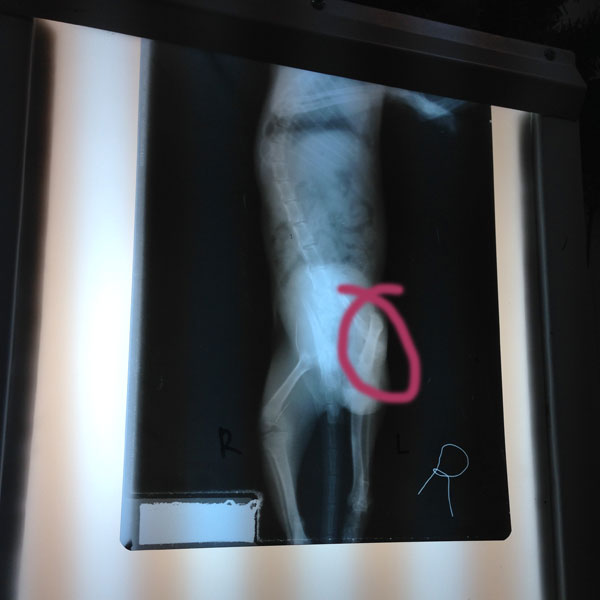

After checking Baby Steps out, the vet (Dr. Jess) suggested that we do an x-ray to see how bad the broken leg is.

Dr. Jess told us that surgery had to be done. Basically, they’ll need to use pins to put back the bones together. He scheduled Baby Steps for surgery next day with Dr. Nielsen Donato.

He examined Baby Steps and told us that while he can do surgery on the leg, he’s unsure if Baby Steps will still be able to make full use of the leg. He wasn’t sure if the nerves were still in-tact and working.

Even if the surgery went well, but the leg was found to be unresponsive, the surgery will be useless.

So he presented another option – to amputate Baby Steps’ left leg.

Before they began the procedure, however, they decided to do another x-ray… whichย was a good thing because the 2nd x-ray showed that the leg could be saved!